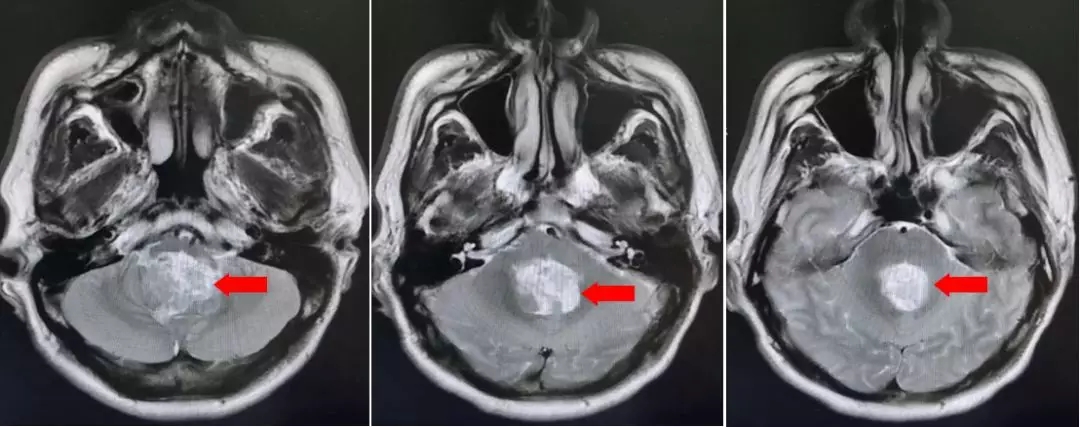

术后复查的核磁,肿瘤全切,未见残留征象。脑积水较术前改善。

术后病理示:室管膜瘤(WHO II级)